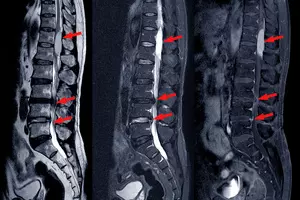

허리 협착증은 척추 퇴행성 변화로 인해 척추관이 좁아져 신경 압박이 발생하는 질환으로, 극심한 통증, 다리 마비, 생활 기능 저하 등을 초래할 수 있습니다. 하지만 적절한 운동을 통해 허리 협착증 증상을 완화하고 삶의 질을 향상할 수 있습니다. 오늘은 이를 위해 허리 협착증에 좋은 운동 9가지에 대해 알아보도록 하겠습니다.